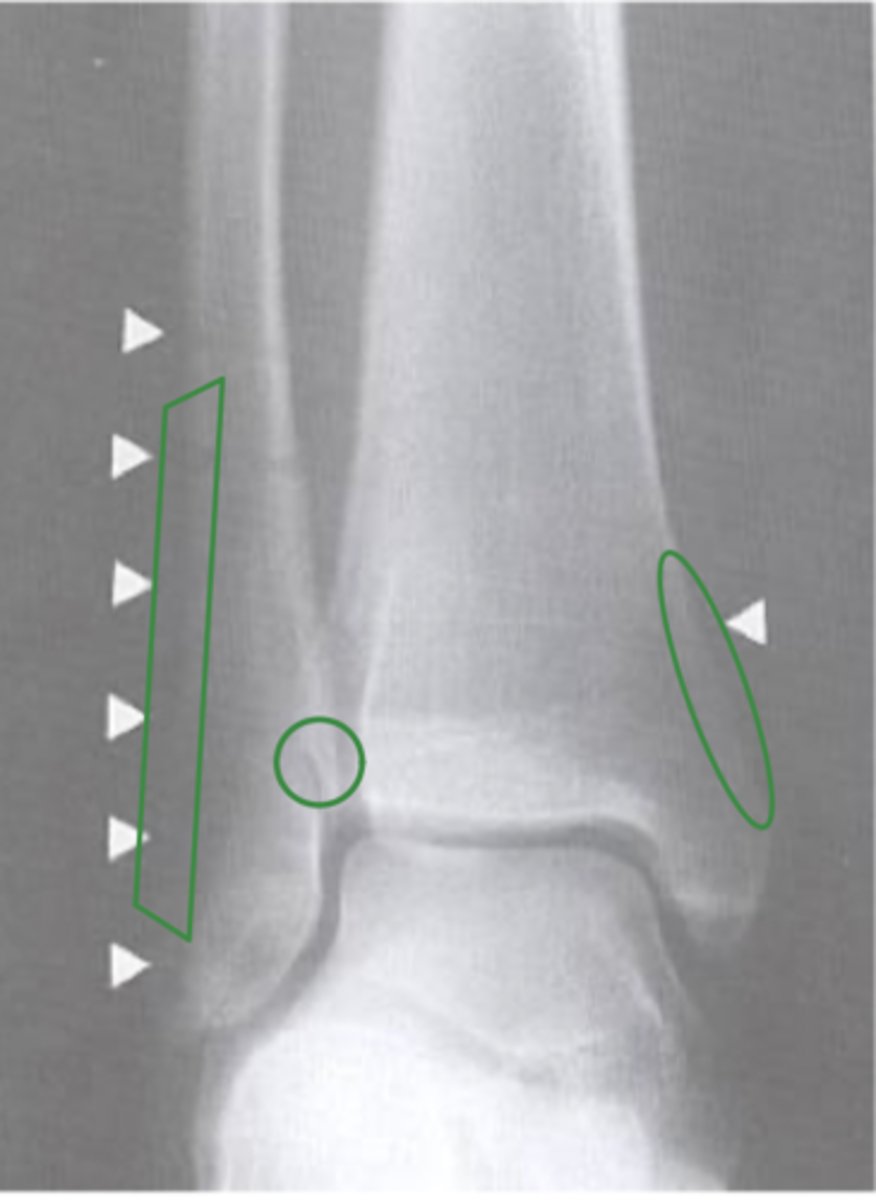

AP of the right ankle

What view does this show?